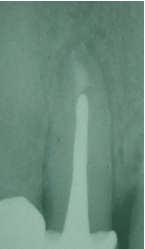

X-ray control after 4 mounth